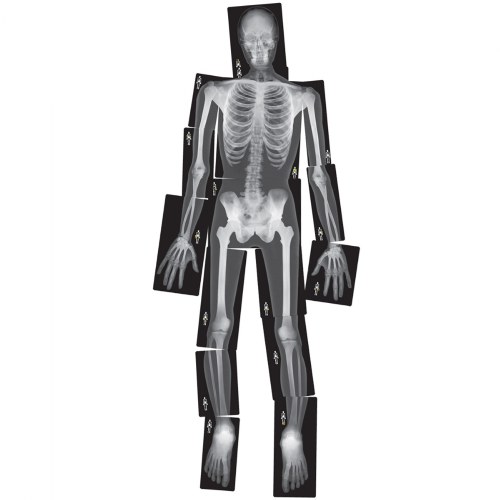

5 years & up. Equip your little doctor with the x-rays of common accidents! These cards will bring a strong realistic element to dramatic play. Real X-rays reveal a detailed look at common breaks in a variety of human bones. Hold up to the light or use it on a light table. An informative guide is included.

- Real X-rays reveal broken bones

Our preschool kids have so much fun exploring X-rays as they pretend to be doctors. Watching the kids find new ways to view images with flashlights, on the light table and against windows is a great way to boost cognitive development as well as their social skills as they work together.

This product is very good for teaching young about their bones and where they are locate on their body my classroom students love it.

I purchased this for our daycare and the kids love them they play doctor all the time with them!! They look real and have held up great with the kids